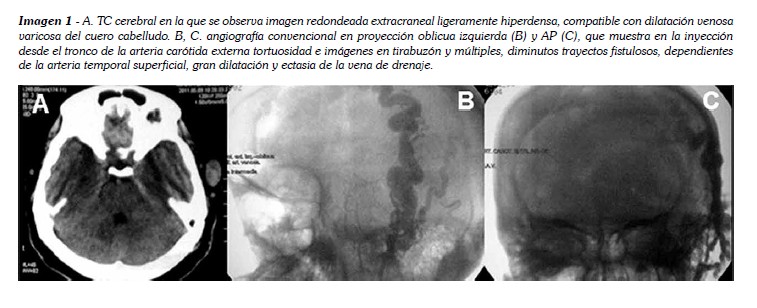

Se le practicó una tomografía cerebral simple, que mostró una lesión isodensa, redondeada, de bordes regulares, extra craneal que se extiende desde la región temporal hasta la región frontal. Se realiza una angiografía convencional en la que se confirma el diagnóstico de una fístula de la arteria temporal superficial, haciendo evidente una arteria temporal superficial tortuosa y con una gran dilatación varicosa de un vaso venoso, desde la línea media en la región frontal hasta un centímetro por debajo del trago izquierdo.